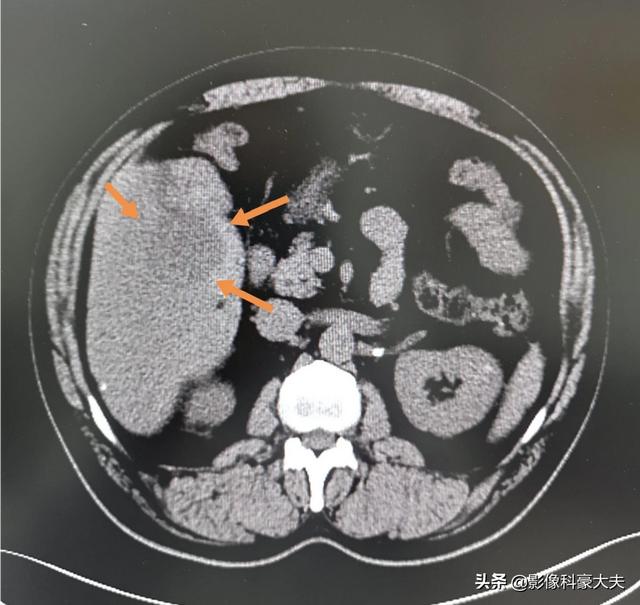

B型慢性肝炎の患者さんで、健康診断で小さな肝臓がんが見つかりました。手術が間に合わなければ、長くて半年で進行癌に進行してしまいます。現代の先端機器のおかげで、この患者さんは発見も手術も間に合い、1年以上経過していますが再発はありません:

いい風は空に届く!